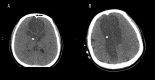

BACKGROUND Pituitary macroadenoma is a common benign tumor that usually presents with visual field defects or hormonal abnormalities. Cerebral infarction can be a complication of a large pituitary adenoma. We report a rare case of bilateral anterior cerebral arteries infarcts by a large pituitary macroadenoma with apoplexy. CASE REPORT A 48-year-old male patient presented with altered conscious level and sudden loss of vision for one-day duration. Magnetic resonance imaging of the brain showed a large seller and suprasellar hemorrhagic mass of pituitary origin, with associated bilateral areas of diffusion restriction in the frontal parasagittal regions, consistent with infarctions. Magnetic resonance angiography showed elevation and compression of A1 segment of both anterior cerebral arteries by the hemorrhagic pituitary macroadenoma. The patient underwent trans-sphenoidal resection of the pituitary adenoma, but unfortunately, ischemia was irreversible. Computed tomography (CT) done post-operatively showed hypodensity in the frontal and parietal parasagittal areas, which was also persistent in the follow up CT scans. The patient's neurological function remained poor, with GCS of 8/15, in vegetative state. CONCLUSIONS Vascular complications of the pituitary apoplexy, although uncommon, can be very severe and life threatening. Early detection of vascular compromise caused by hemorrhagic pituitary macroadenoma can prevent delay in intervention. Clinicians should also consider pituitary adenoma as a possible cause of stroke.